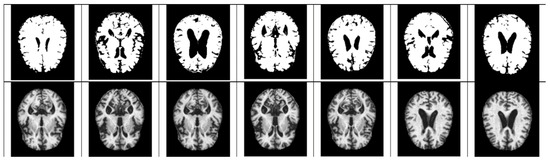

- For Z-score normalization, the interval to which each pixel belongs is converted to [−1, 1], and for min–max, it is converted to [0, 1]. During the computation of the convolutional neural network, the pixel intensity of [0, 255] is adjusted for fast convergence and accurate feature extraction.

- The size space of pixels constituting the Alzheimer’s MRI data set is [0, 255]. Among them, patients with AD with reduced hippocampus will have more pixels close to zero than normal people. On the premise of this, the average value of pixel intensities in each MRI image is set as a threshold value. Alzheimer’s should recognize changes in size contraction rather than changes in brain function. Based on this information, it is necessary to set the space as an important feature for the color information of MRI rather than a feature representing the shape of the brain.